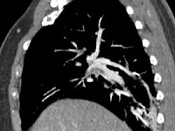

- 单项选择题男,56岁, 食管癌术后,胸痛, 呼吸困难,结合CT图像, 最可能的诊断是 ( )

B、肺栓塞